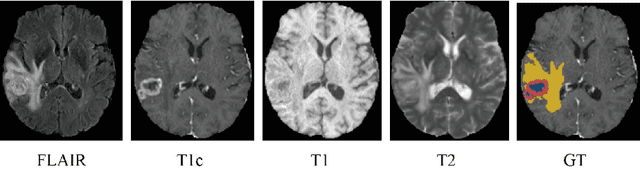

Abstract:In the field of multimodal segmentation, the correlation between different modalities can be considered for improving the segmentation results. Considering the correlation between different MR modalities, in this paper, we propose a multi-modality segmentation network guided by a novel tri-attention fusion. Our network includes N model-independent encoding paths with N image sources, a tri-attention fusion block, a dual-attention fusion block, and a decoding path. The model independent encoding paths can capture modality-specific features from the N modalities. Considering that not all the features extracted from the encoders are useful for segmentation, we propose to use dual attention based fusion to re-weight the features along the modality and space paths, which can suppress less informative features and emphasize the useful ones for each modality at different positions. Since there exists a strong correlation between different modalities, based on the dual attention fusion block, we propose a correlation attention module to form the tri-attention fusion block. In the correlation attention module, a correlation description block is first used to learn the correlation between modalities and then a constraint based on the correlation is used to guide the network to learn the latent correlated features which are more relevant for segmentation. Finally, the obtained fused feature representation is projected by the decoder to obtain the segmentation results. Our experiment results tested on BraTS 2018 dataset for brain tumor segmentation demonstrate the effectiveness of our proposed method.

Abstract:In the field of multimodal segmentation, the correlation between different modalities can be considered for improving the segmentation results. In this paper, we propose a multi-modality segmentation network with a correlation constraint. Our network includes N model-independent encoding paths with N image sources, a correlation constraint block, a feature fusion block, and a decoding path. The model independent encoding path can capture modality-specific features from the N modalities. Since there exists a strong correlation between different modalities, we first propose a linear correlation block to learn the correlation between modalities, then a loss function is used to guide the network to learn the correlated features based on the linear correlation block. This block forces the network to learn the latent correlated features which are more relevant for segmentation. Considering that not all the features extracted from the encoders are useful for segmentation, we propose to use dual attention based fusion block to recalibrate the features along the modality and spatial paths, which can suppress less informative features and emphasize the useful ones. The fused feature representation is finally projected by the decoder to obtain the segmentation result. Our experiment results tested on BraTS-2018 dataset for brain tumor segmentation demonstrate the effectiveness of our proposed method.